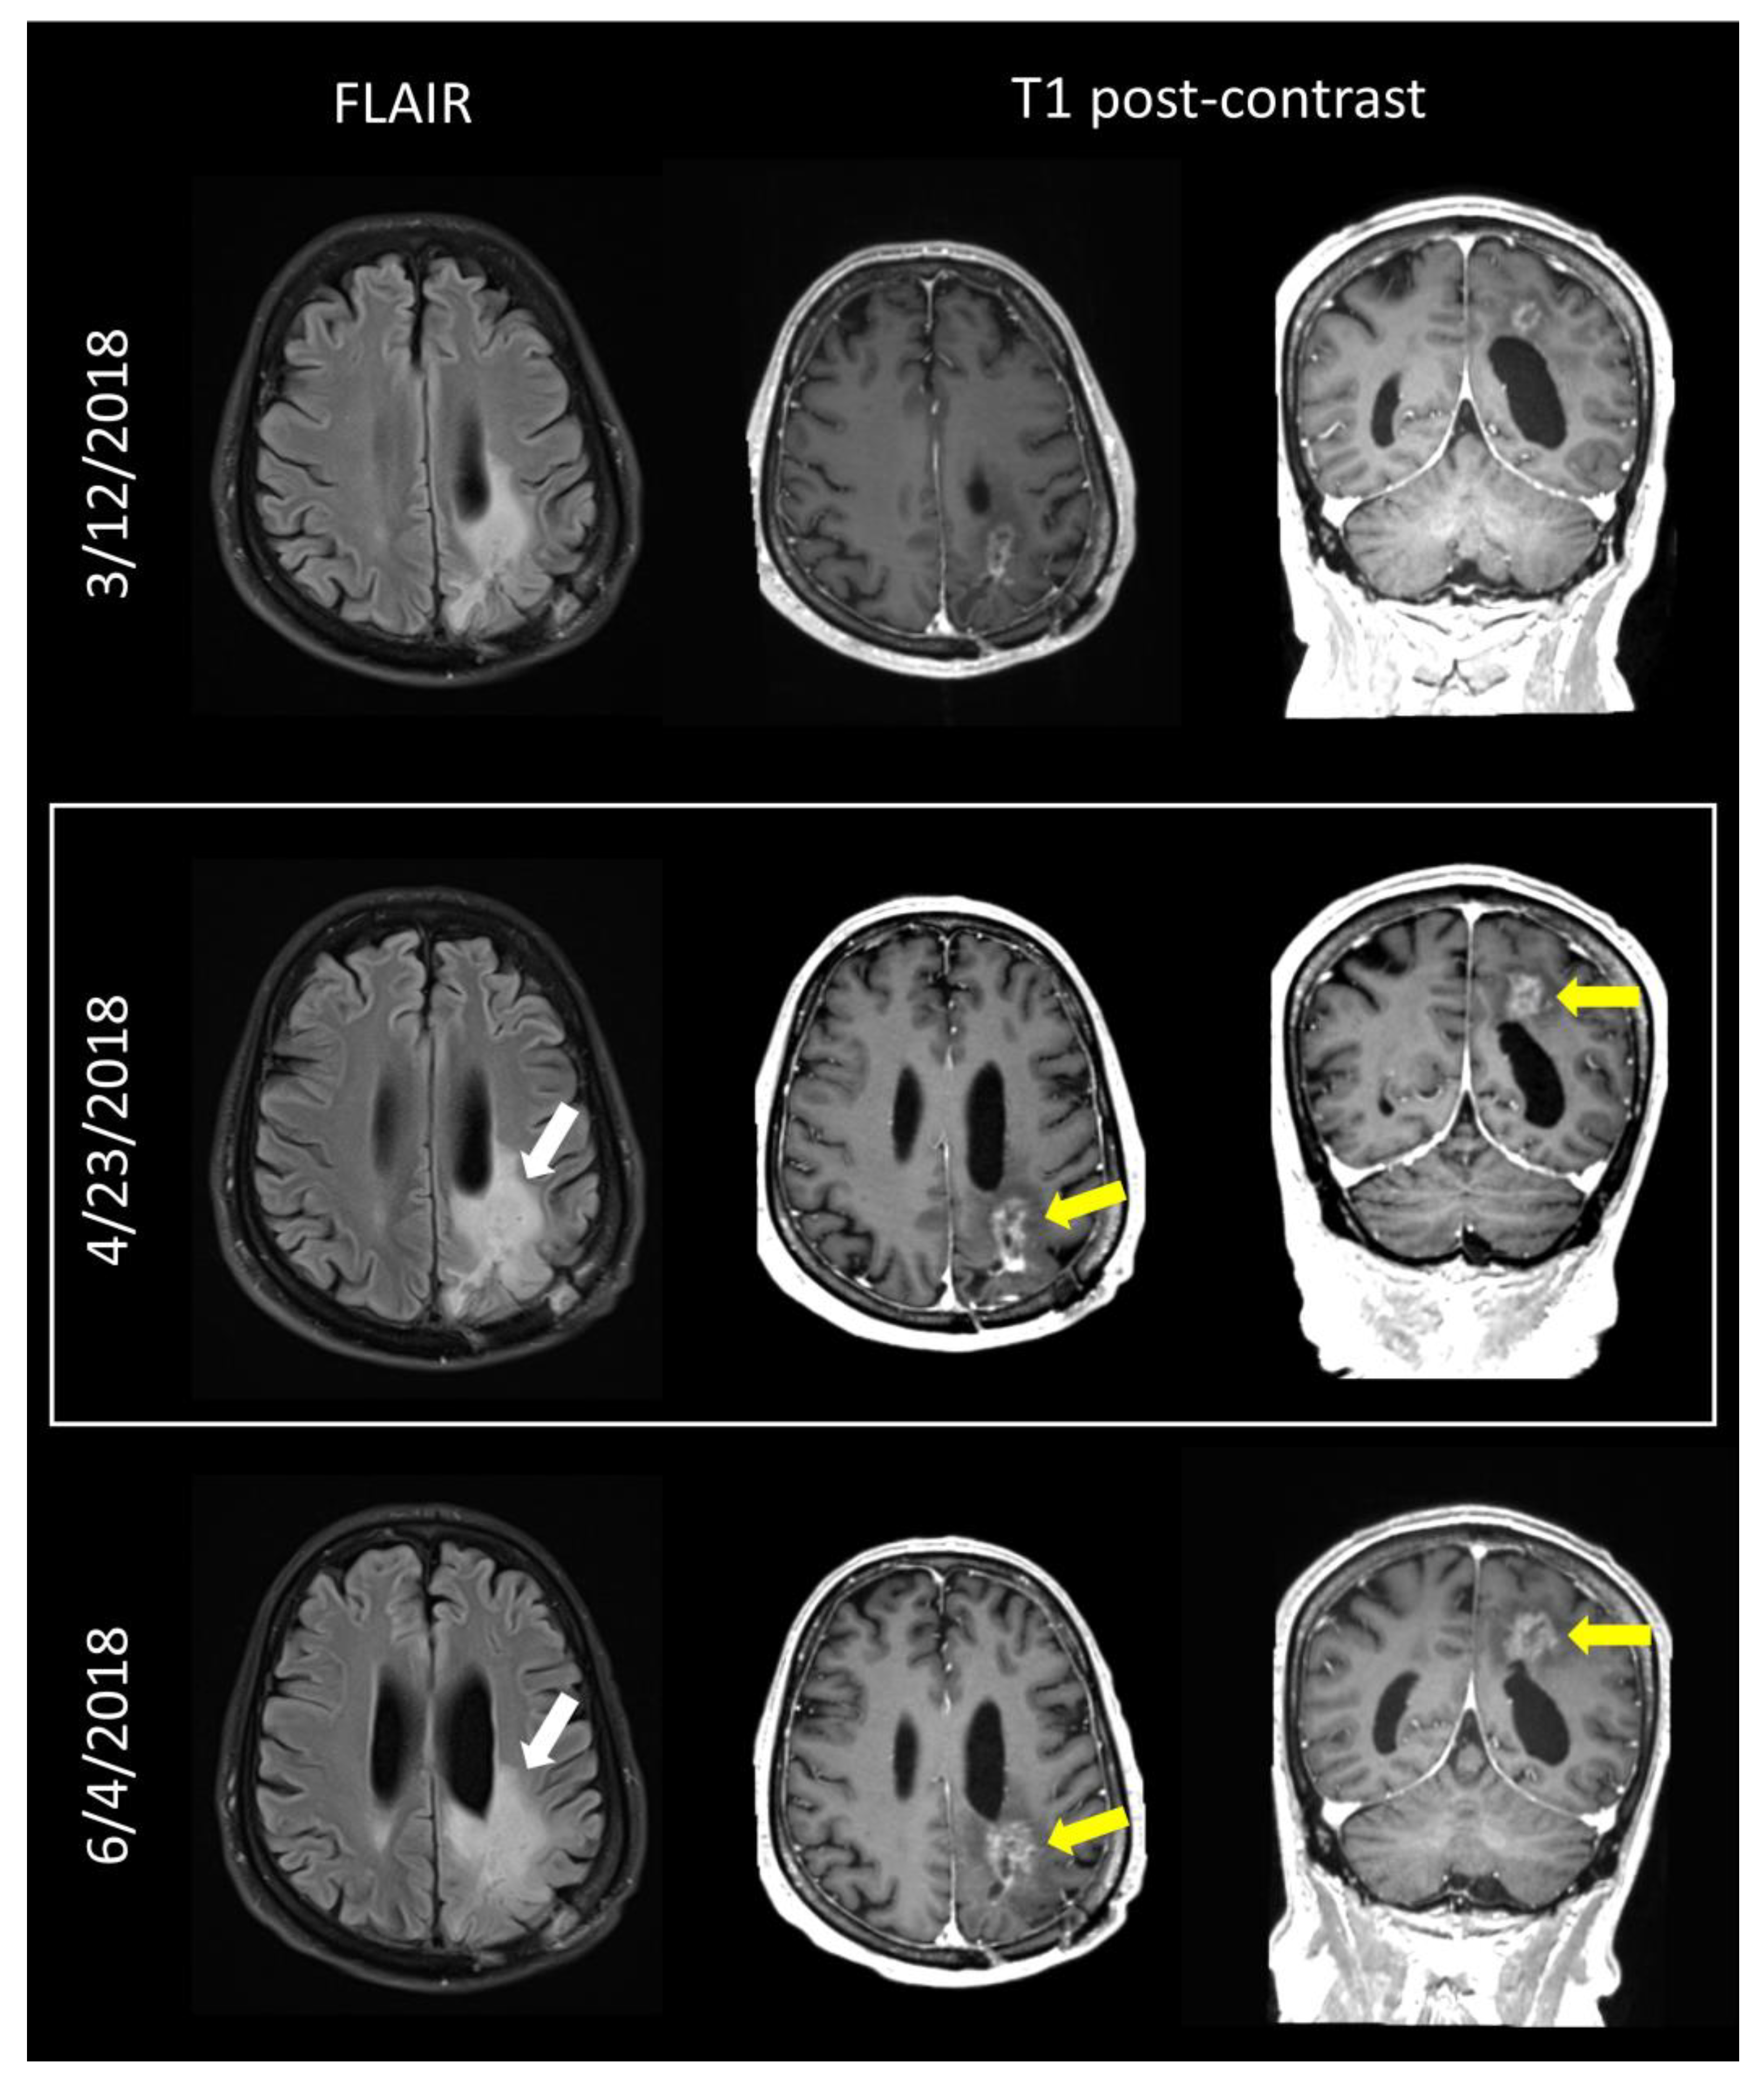

- Weinberg, B.D.; Gore, A.; Shu, H.G.; Olson, J.J.; Duszak, R.; Voloschin, A.D.; Hoch, M.J. Management-Based Structured Reporting of Posttreatment Glioma Response with the Brain Tumor Reporting and Data System. J. Am. Coll. Radiol. 2018, 15, 767–771. [Google Scholar] [CrossRef]

- Gore, A.; Hoch, M.J.; Shu, H.G.; Olson, J.J.; Voloschin, A.D.; Weinberg, B.D. Institutional Implementation of a Structured Reporting System: Our Experience with the Brain Tumor Reporting and Data System. Acad. Radiol. 2019, 26, 974–980. [Google Scholar] [CrossRef] [PubMed]

- Zhang, J.Y.; Weinberg, B.D.; Hu, R.; Saindane, A.; Mullins, M.; Allen, J.; Hoch, M.J. Quantitative Improvement in Brain Tumor MRI Through Structured Reporting (BT-RADS). Acad. Radiol. 2020, 27, 780–784. [Google Scholar] [CrossRef]